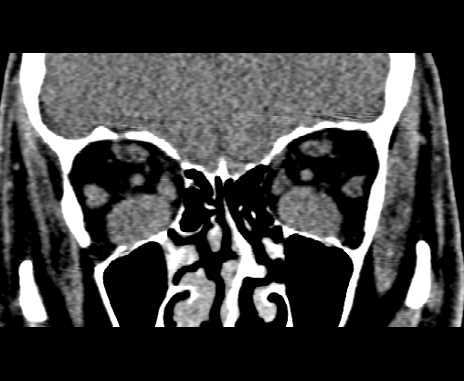

https://www.researchgate.net/figure/Bilateral-Sturge-Weber-syndrome-Postcontrast-axial-MR-image-A-shows-gross_fig1_14472655

Bilateral Sturge-Weber syndrome. Postcontrast axial MR image ( A ) shows gross leptomeningeal thickening and enhancement related to the right hemisphere and less extensive abnormality of the left occipital region. Unenhanced axial T1-weighted image ( B ) shows thickening of the posterior globes bilaterally; after administration of contrast material ( C ), marked enhancement is seen in both globes. Abnormal high signal is present in this region on the proton density–weighted image ( D ). Bilateral, diffuse choroidal hemangiomas were found at ophthalmoscopy (not shown).